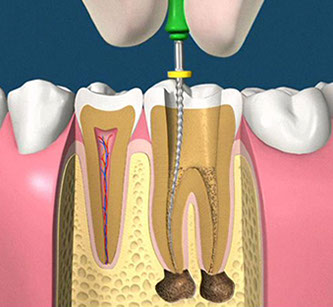

• accesso alla camera pulpare mediante frese diamantate

• asportazione della polpa e sagomatura dello spazio endodontico con strumenti meccanici (in nichel-titanio), con l'ausilio della detersione del canale radicolare (acqua ossigenata, ipoclorito di Sodio, calcio-chelanti)

• otturazione di tutto l'endodonto mediante materiali termoplastici (guttaperca) e cementi biocompatibili

• controllo radiografico